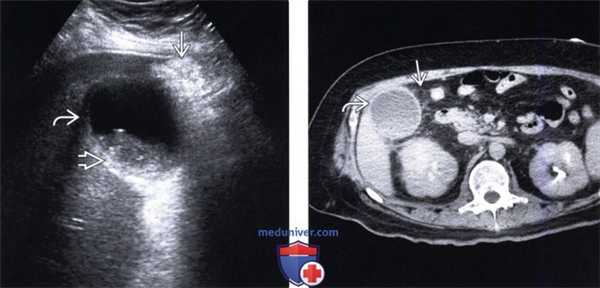

(Левый) На продольном косом УЗ срезе у пациента с острым веска менным холециститом с гангреной, перенесшего трансплантацию легкого, визуализируется растянутый желчный пузырь, содержащий вязкий сладж. Стенка желчного пузыря утолщена, ее контур имеет дефекты.

(Правый) На продольном косом срезе у того же пациента определяется гиперемия перипузырной зоны, признаки кровотока в некротизированной стенке отсутствуют.